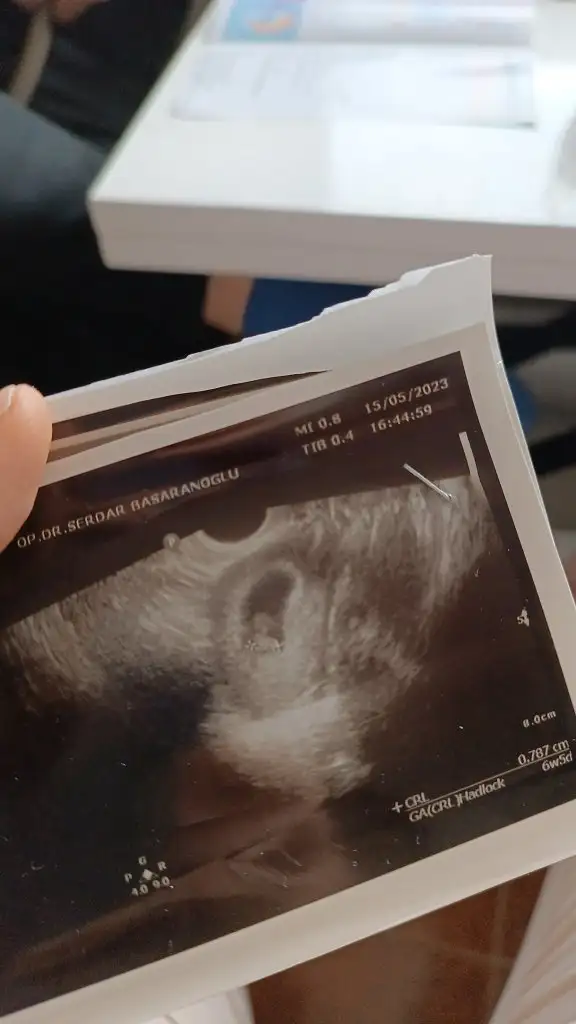

Kızlar keseye göre cinisiyet tahmini alabilir miyim❤️😂😂

Eklentiler

• IMG-20230515-WA0004.webp

IMG-20230515-WA0004.webp

20,1 KB · Görüntüleme: 72